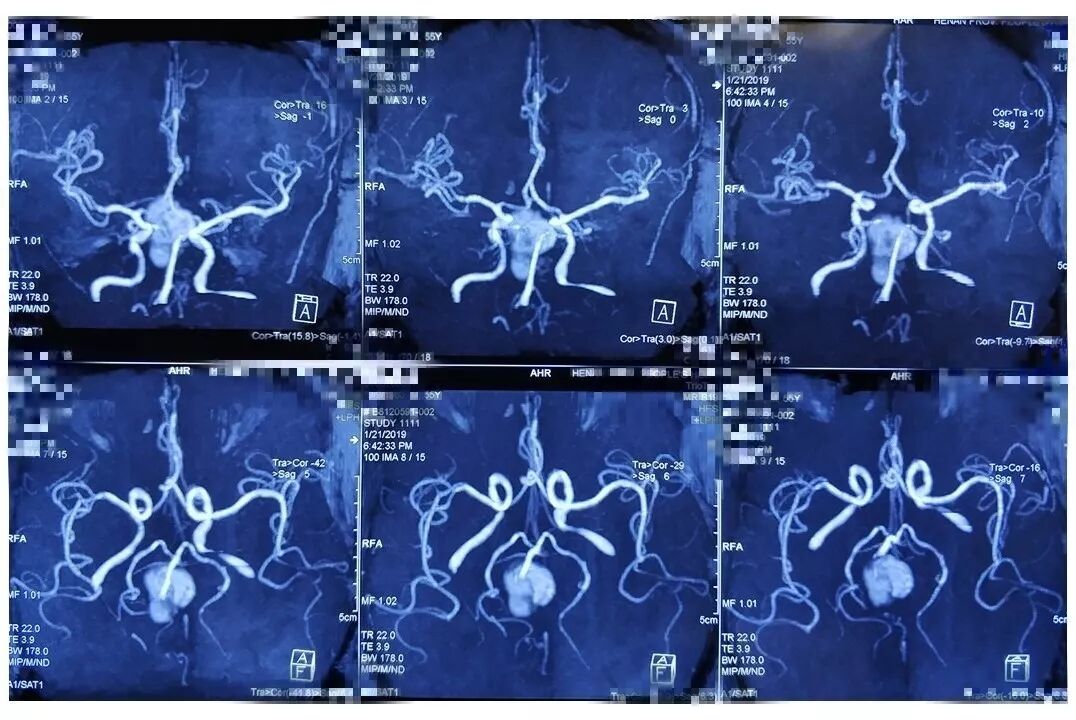

术前影像:透明隔腔明显增宽,双侧脑室、三脑室、脚间池明显扩张、积水,周围脑实质受压,胼胝体受压变薄。弥散加权图像未见异常。中线结构居中。增强扫描未见异常强化。

术前诊断:三脑室内囊肿,幕上脑积水。